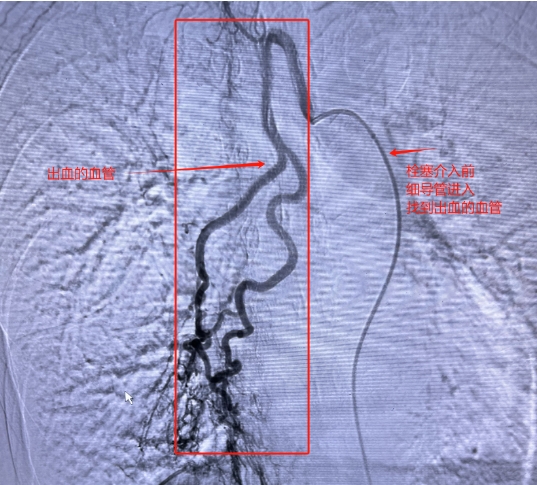

情况十分危急,肿瘤科蒋秀清主任赶来会诊。经过仔细检查和评估,蒋主任决定采用经导管介入栓塞治疗。这就好比是给 “决堤” 的血管 “堵口子”—— 通过一根细细的导管,找到出血的血管,再用特殊的材料把它堵住。

在和阿姨的家人详细沟通,征得他们同意后,医生们迅速为阿姨完善了各项检查,并马上进行了急诊手术。手术中,医生们全神贯注,精准操作,成功完成了经导管选择性支气管动脉栓塞治疗。

蒋秀清主任团队行经导管选择性支气管动脉栓塞治疗